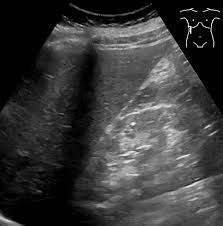

복부 초음파는 간, 담낭, 췌장, 비장, 신장, 방광, 복부 대혈관 등 주요 장기를 대상으로 시행됩니다.

검사 부위가 넓은 만큼 발견 가능한 복부 초음파로 알 수 있는 것(질환)의 스펙트럼도 상당히 다양합니다. 다만 초음파는 “구조적 이상”을 중심으로 확인하는 검사이므로, 기능적 이상이나 아주 초기 단계의 미세 병변은 한계가 있다는 점을 전제로 이해하시는 것이 좋습니다.